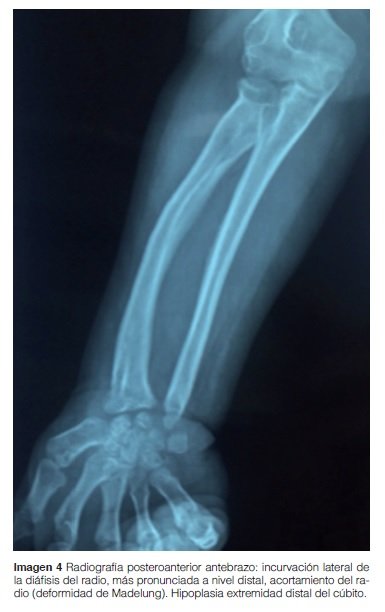

Antebrazo: Cúbito hipoplásico con curvatura del radio hacia cúbito más marcado a nivel distal (deformidad de Madelung) (Imagen 4).